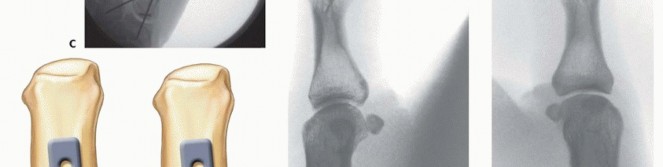

Closed Reduction and Percutaneous Pinning (CRPP)

CRPP is the treatment of choice for classic Bennett fractures where the volar-ulnar fragment is too small to reliably accept a lag screw, yet the joint can be anatomically reduced closed. The reduction maneuver is highly specific, designed to counteract the deforming forces of the APL and Adductor Pollicis. Longitudinal traction is applied to the thumb, followed by palmar abduction and pronation. Direct pressure is then applied to the dorsal-radial aspect of the metacarpal base, effectively pushing the shaft back into the anatomic cradle of the intact volar-ulnar fragment.

Once anatomic reduction is confirmed via multi-planar fluoroscopy, percutaneous fixation is achieved. Typically, two 0.045-inch or 0.062-inch Kirschner wires are utilized. The first wire is driven from the dorsal-radial aspect of the metacarpal shaft directly into the trapezium, effectively neutralizing the proximal pull of the APL. A second wire is often placed transversely from the first metacarpal shaft into the second metacarpal to control rotation and maintain the web space. Pins are cut outside the skin and capped to facilitate easy removal in the clinic.

Image